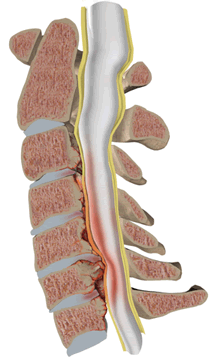

Оссификация ЗПС приводит к уменьшению передне-заднего диаметра спинномозгового канала, что приводит к стенозу спиннопозвоночного канала, сдавление спинного мозга.

Стеноз (сужение) просвета позвоночного канала со сдавлением спинного мозга с гипертрофией задней продольной и жёлтой связки.

Стеноз позвоночного канала со сдавлением спинного мозга при спондилёзе на уровне шейного отдела позвоночника с гипертрофией задней продольной и жёлтой связки.